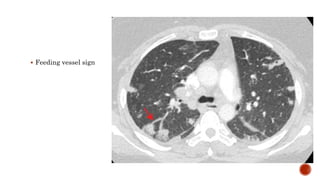

 Distribution :

 Peripheral

 Lower lobe predominance

 Multiple

 Bilateral

 Varying stages of cavitation

 Feeding vessel sign

 Complications :

 Empyema

 Pneumothorax